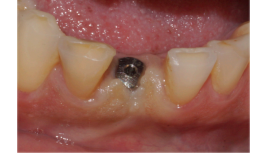

Após os três meses, foi realizada a abertura do implante e foi instalado um cicatrizador, que permaneceu no local por dez minutos para manter os tecidos afastados.

Após esse período, foi selecionado o pilar, e um Pilar Ideale reto de 3.3 X 4.0 X 1.5 mm foi instalado e torqueado a 20 Ncm (Figuras 13 e 14).